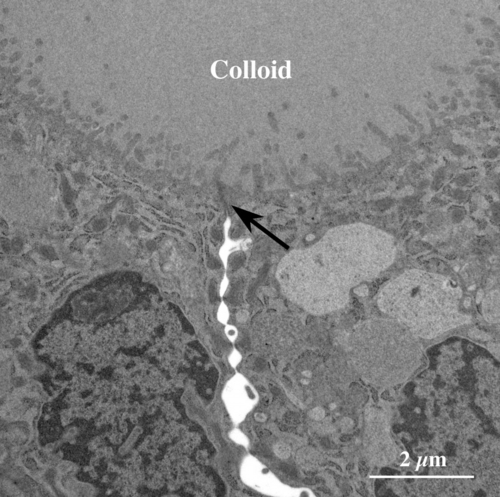

【 薄さ70 - 80 nm 超薄切片の透過型電子顕微鏡画像 】

Transmission electron microscopic image of 70 - 80 nm ultrathin section

濾胞上皮細胞頂上部の拡大像

上皮細胞間をつなぐタイト結合(矢印)